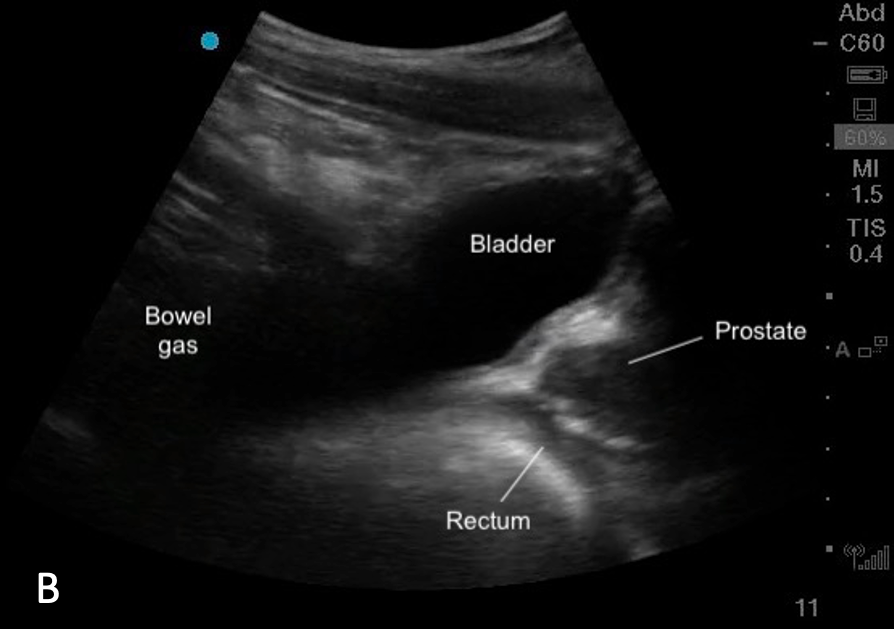

Position

The bladder sits in the pelvis just posterior to the pubic symphysis. Its size and position relevant to other structures varies according to bladder fullness.

> Full Bladder:

– Sits anterior to the uterus in females (figure 7a, 9a)

– Sits cranial and anterior to the prostate in males (Figure 7b,9b)

– Anterior to the rectum

– Remains anterior to the prostate in males but is positioned lower in the pelvis

– Anterior to the rectum (figure 8)

Figure 7ab: Sagittal bladder sonoanatomy in female (a) and male (b) children.

Figure 9ab: Transverse bladder scan sonoanatomy in female (a) and male (b) chidlren.